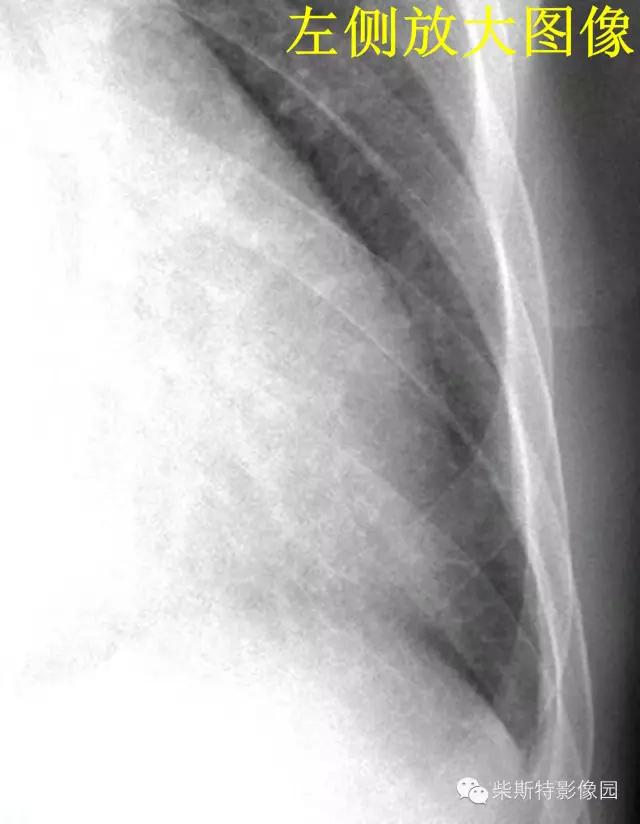

2.B线:为克氏线征中最常见者,表现为较短的不分又的梯状致密横线影,长不超过2cm,宽不超过1mm。常位于两下肺野的外带(肋隔角)平行的次出现,亦可见于中肺野,但从不出现于上肺野。其外端常抵达胸膜缘并与之垂直,以右侧为多见.